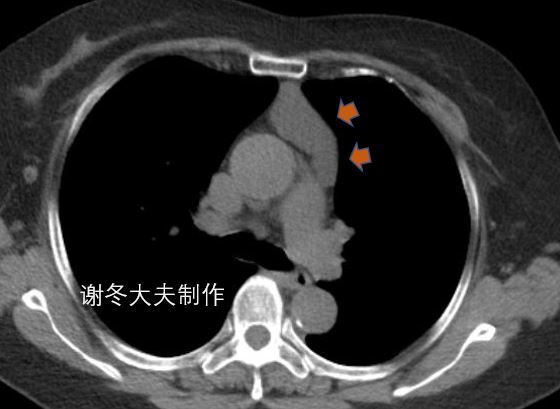

2.侵袭性胸腺瘤

侵袭性胸腺瘤明确的CT征象:纵隔结构的包绕,直接侵犯中心静脉、心包或胸膜种植转移和晚期发生的跨膈肌扩散。

侵犯上腔静脉,伴有双侧胸水